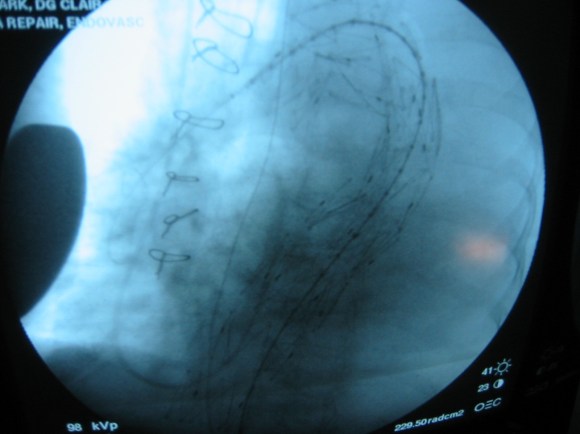

The common femoral endarterectomy is done from its distal most point and the Vollmer ring is used to mobilize the plaque. A Moll Ring Cutter (LeMaitre Vascular) is then used to cut the plaque.

The plaque is extracted and re-establishes patency of the EIA.

The plaque end point is typically treated with a stent -in this case, the common iliac plaque was also treated.